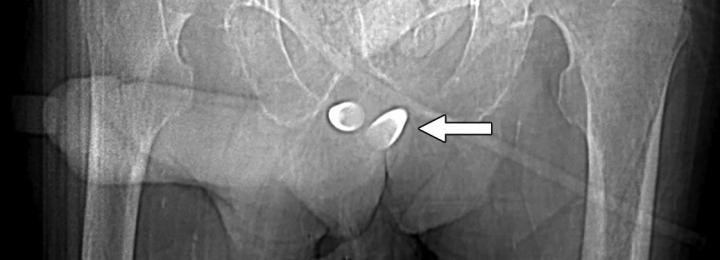

image: Scout image from contrast-enhanced CT shows erectile implant; stainless steel and silicone anchors (arrow) transfixed to pubic bone are asymmetric.

When evaluating urethral complications from phalloplasty in trans-males, because the neo-to-native urethra anastomosis site will evidence diameter differences, retrograde urethrograms can result in stricture overdiagnosis. Apropos, preliminary assessments should be for functional stricture, alongside the performance of urodynamic studies. "However," notes Doo, "for confirmation of stricture with abnormal function tests and also for evaluation for fistula, a retrograde urethrogram or voiding cystourethrogram can be obtained." Should a patient desire erectile potential with the fully-healed neophallus, an implant may be placed, which is prone to infection, attrition, malposition, and constituent separation.